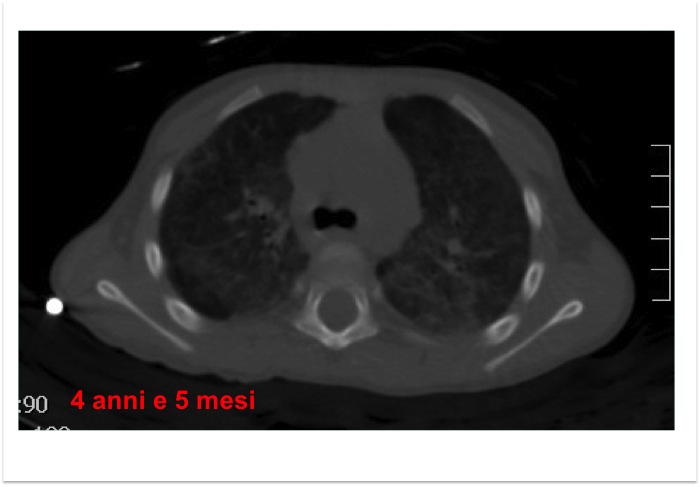

Viene pertanto eseguita una TC torace (Figura 5): aumentata densit� diffusa con pattern a �vetro smerigliato�. La conferma diagnostica di alveolite emorragica � stata ottenuta grazie al ritrovamento di numerosi siderofagi al lavaggio bronco-alveolare (Figura 6).

Figura 5. TC torace eseguita a 4 anni e 5 mesi.